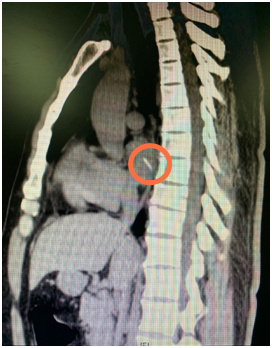

胸部CT片 画圈处为鱼刺

福建省立医院心外科主任医师谢琦分析,这根刺刺穿食管后,随着阿福的不断进食吞咽,又刺进了邻近的左心房并被完全推了进去。来自唾液和鱼刺上的细菌从被扎的破口向外侵袭并不断繁殖,导致阿福出现血液感染并诱发高烧。由于人体的食管和心肌几乎没有痛觉,耽误了阿福找到病因。